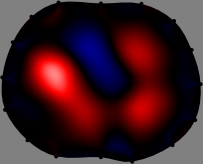

Figs. 3 and 4 compare the performance of the proposed FER method in (20) with the standard regularized least-squares method ((19) when \mathcal{R} is the identity matrix). The regularization parameter of the standard method was heuristically chosen for its best performance, and the parameter of the FER method was set to be one of three different values λ=0.05,0.2,𝜆0.050.2\lambda=0.05,0.2,\infty. The injection current was 1 mARMSRMS{}_{\tiny{\mbox{RMS}}} at 100 kHz, and the frame rate was 9 frames per second. The reference frame at t0subscript𝑡0t_{0} was obtained from the maximum expiration state. The measured data, 𝐕˙(tm)˙𝐕subscript𝑡𝑚\dot{\mathbf{V}}(t_{m}), represent the voltage differences between each time tmsubscript𝑡𝑚t_{m} and t0subscript𝑡0t_{0}. The blue regions, which denote where conductivity decreased by inhaled air, increased during inspiration and decreased during expiration. The FER method with λ=𝜆\lambda=\infty was clearly more robust than the standard method that produced more artifacts originated from the inversion process.

Figure 3: The reconstructed images of the conductivity change of the subject A by the standard regularized least square method and the proposed fidelity-embedded regularization (FER) method for three difference values λ=0.05,0.2,𝜆0.050.2\lambda=0.05,0.2,\infty. Here, the time step is 0.22 seconds (tm+2tm0.22subscript𝑡𝑚2subscript𝑡𝑚0.22t_{m+2}-t_{m}\approx 0.22).